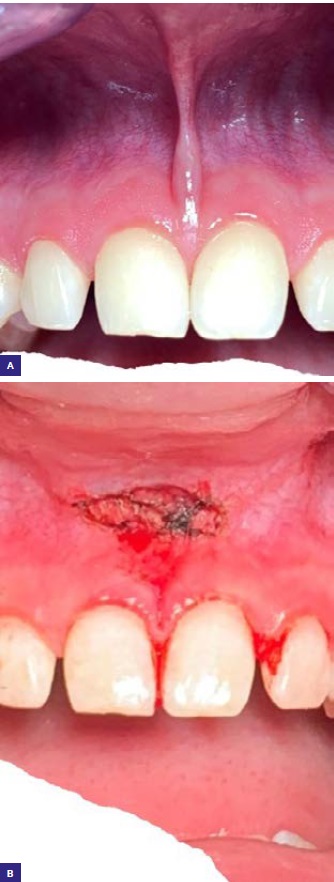

Ryc. 1. Korekta przyczepu wędzidełka wargi laserem CO2. A. przed zabiegiem; B. po zabiegu.